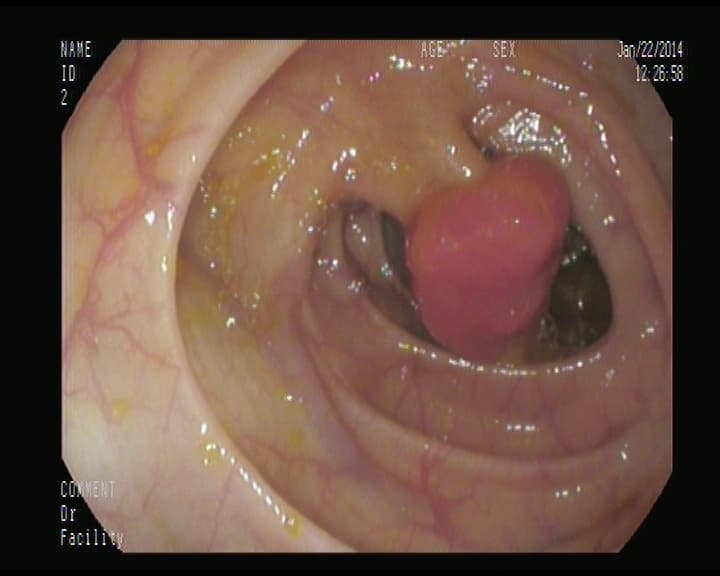

Pólipo adenomatoso, con pedículo ancho

Deben ser resecados para su analisis histólogico, y confirmar que es pólipo que se transformaría en cáncer. Esto no da sintomatología, una sangre oculta en heces, nos puede inducir a realizar colonoscopia y detectarlos.